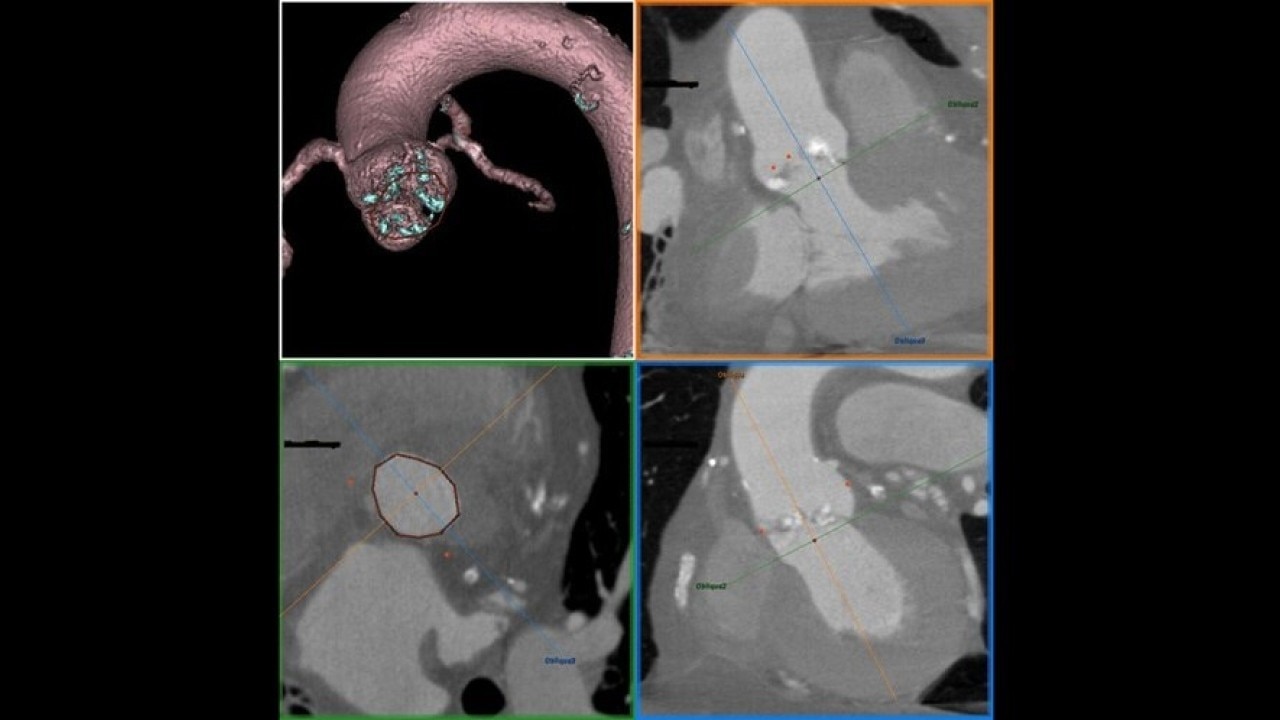

The Valve Planning protocol in the VesselIQ Xpress application lets you visualize cardiac anatomy with the degree of detail required to evaluate the presentation of the aortic valve. Armed with this information, you can develop a pre-procedural TAVR/TAVI plan to establish a therapy strategy for the patient.